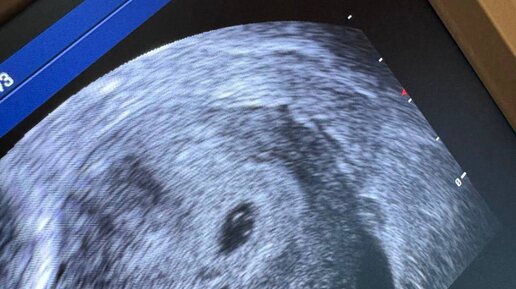

Репродуктолог Владимирова Инна

Здесь беременность 4-5 нед, самого малыша пока не видно, то видим желточный мешочек , значит беременность развивается